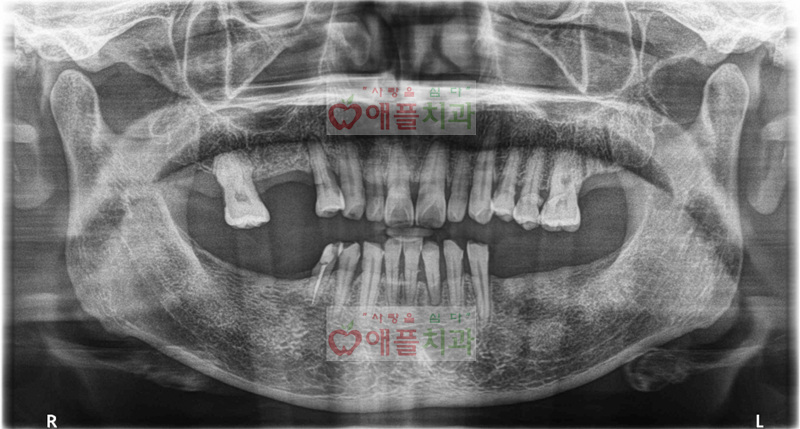

<내원 당일 엑스레이>

소개로 오신 환자 분입니다.

컴퓨터분석 임플란트 환자분의 소개로 임플란트 상담 받으시러 내원하셨습니다.